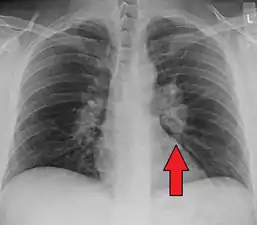

- Hilar adenopathy especially on the person's left (AP CXR)

- Hilar adenopathy especially on the person's left (lateral CXR)